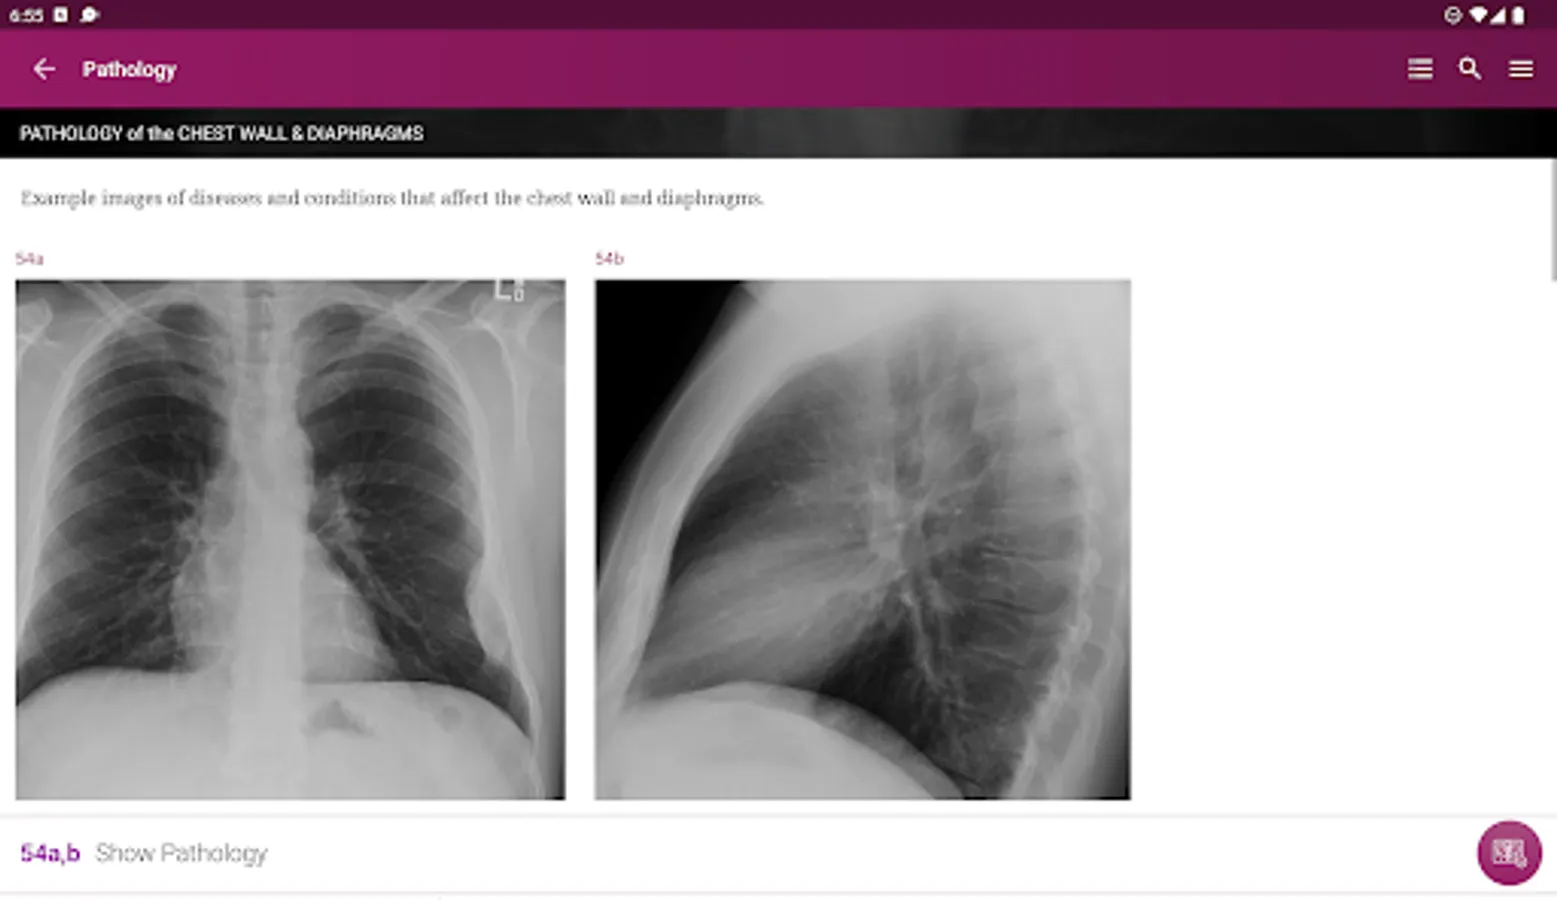

Pathology – Numerous interesting examples of pathology related to specific anatomical structures and regions.